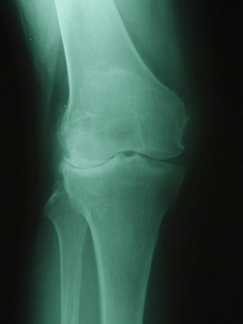

Question 8

Question

Which disease is shown

Answer

• Pagets

• OA

• RA